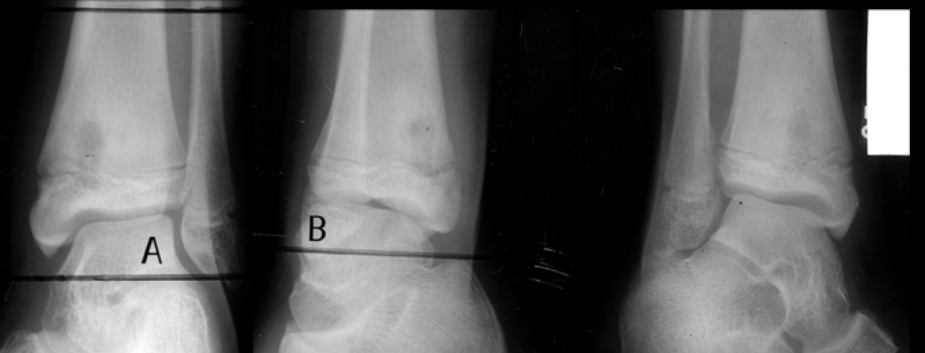

3

Q

What are the present soft tissue findings?

A

• Soft tissue emphysema

• Sequestrum

• Swelling

osteomyelitis